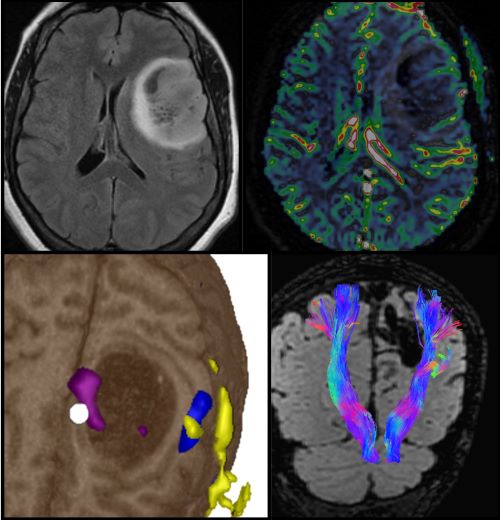

• Neuroradiology →

Neuroradiology

The mission of the Neuroradiology Fellowship Program is to provide an in-depth, comprehensive neuroimaging experience, and expose fellows to research, quality assurance methods and leadership initiatives. Fellows train in a supportive, collegial, tertiary care hospital setting that enables them to provide outstanding health care, contribute to advancing medical knowledge and achieve their career goals.